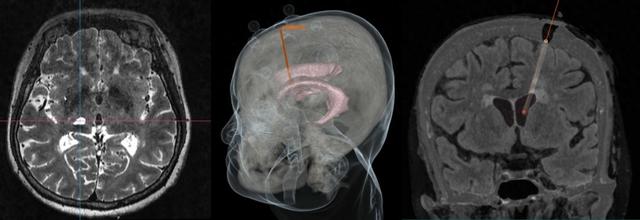

手术计划及术后效果图

手术前,徐纪文医生团队将柏阿姨的相关资料导入手术机器人系统,生成直观精确的3D数字化模型,可视化呈现柏阿姨脑室情况,规划出理想的术中穿刺点和手术方案。